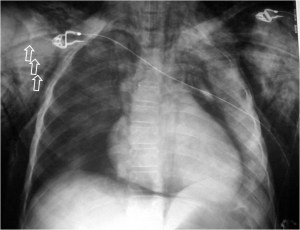

SIGNO DEL TUMOR FANTASMA O TUMOR EVANESCENTE

Signo que describe al derrame pleural atrapado en la cisura menor, especialmente en pacientes con insuficiencia cardiaca. El derrame loculado en la proyección posteroanterior se ve como una lesión nodular o masa que simula un tumor sólido (imagen superior). Sin embargo, la evolución rápida hacia la desaparición de esta lesión sugiere que se trata de derrame.

Vemos en las imágenes un tumor fantasma que desaparece en el control realizado cinco días más tarde.

En la primera imagen, la presencia de derrame pleural asociado y el engrosamiento del resto de la cisura menor, visible como una línea superpuesta al tumor fantasma, sugieren el diagnóstico.